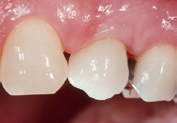

Für den Knochenaufbau wurde Geistlich Bio-Oss Collagen in den Defekt appliziert und nach der Augmentation die Eingriffsstelle mit einem Kollagenvlies abgedeckt. Weitere 6 Monate nach dem Eingriff wurde die endgültige Kronenrestauration eingesetzt. Bei der weiteren Nachuntersuchung nach nunmehr 25 Jahren zeigte die Röntgenaufnahme ein stabiles Implantatlager und das klinische Bild bei der Nachkontrolle einen ästhetischen Zahnstatus.